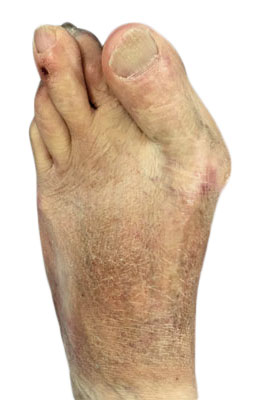

Before

Lapidus Forever Bunionectomy™ and Hamertoe Correction before

After

Lapidus Forever Bunionectomy™ and Hamertoe Correction after

Lapidus Forever Bunionectomy™ and Hamertoe Correction

Amanda is a 37-year-old mother who could not take much time off her foot and needed correction of a very large bunion (hallux valgus) that had also resulted in a hammertoe and partial discoloration of the 2nd toe joint. Amanda had a Lapidus Forever Bunionectomy™ and was back on her foot at 2 weeks after surgery and able to take care of her young children while she healed. Her bunion correction results are amazing, and her foot is fully back to normal.